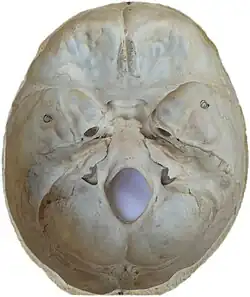

Contusions occur primarily in the cortical tissue, especially under the site of impact or in areas of the brain located near sharp ridges on the inside of the skull. The brain may be contused when it collides with bony protuberances on the inside surface of the skull.[8] The protuberances are located on the inside of the skull under the frontal and temporal lobes and on the roof of the ocular orbit.[9] Thus, the tips of the frontal and temporal lobes located near the bony ridges in the skull are areas where contusions frequently occur and are most severe.[10] For this reason, attention, emotional and memory problems, which are associated with damage to frontal and temporal lobes, are much more common in head trauma survivors than are syndromes associated with damage to other areas of the brain.[11]